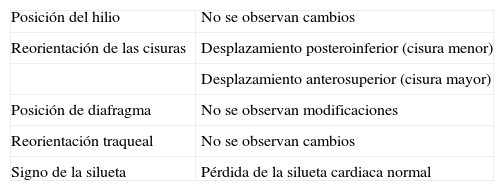

La atelectasia pulmonar es un indicador importante de una enfermedad subyacente, potencialmente grave, que es imprescindible diagnosticar precozmente. Uno de los mecanismos más frecuentes es la reabsorción de aire distal a la obstrucción de las vías respiratorias. La radiografía de tórax es una herramienta excelente para diagnosticarla, especialmente útil para descartar obstrucciones bronquiales centrales (por ejemplo, una neoplasia endobronquial). Si no se reconocen correctamente los signos de la pérdida de volumen el diagnóstico y el tratamiento pueden retrasarse. En este artículo se describen los principales hallazgos radiográficos de la atelectasia pulmonar lobular y su correlación con la tomografía computarizada. Se incluyen los signos clásicos descritos en la bibliografía y otros menos conocidos y a su vez sutiles.

Atelectasis is an important indicator of potentially severe underlying disease that must be diagnosed as early as possible. One of the most common mechanisms is the reabsorption of air distal to respiratory tract obstruction. The chest X-ray is an excellent tool to diagnose atelectasis, and it is especially useful for ruling out central bronchial obstructions (e.g., from endobronchial tumors). If the signs of volume loss are not recognized correctly, the diagnosis and treatment can be delayed. This article describes the main findings of lobar atelectasis on chest X-rays and their correlations with CT findings, including the classic signs described in the literature and other, less known and sometimes subtle signs.